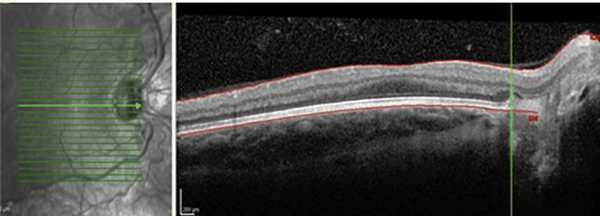

Оптическую когерентную томографию (ОКТ) проводили с помощью прибора Spectralis HRA+OCT («Heidelberg Engineering», Germany).

Задняя РН первой зоны (1-й тип) характеризовалась выраженной сосудистой активностью в заднем полюсе с расширенными, извитыми сосудами и сосудистыми аркадами-анастомозами на границе с аваскулярной сетчаткой, экссудацией в субретинальном пространстве, геморрагическим компонентом, присутствующим в заднем полюсе. Одним из признаков прогрессирования задней РН первой зоны являлись изменения переднего отдела глаза: опалесценция роговицы, рубеоз радужки, ригидность зрачка, экссудация в стекловидном теле, что затрудняло проведение офтальмоскопии (рис. 3). Рисунок 3. Рубеоз радужки при задней РН первой зоны. При этом типе РН отсутствует стадийность процесса, заболевание стремительно прогрессирует с развитием экстраретинальной пролиферации нетипичной, центральной локализации (у ДЗН, вдоль сосудов, не связанная с границей с бессосудистой сетчаткой). Тяжесть процесса при 1-м типе РН первой зоны подтверждалась данными ОКТ: наряду с расширенными, извитыми сосудами отмечался кистовидный отек в макуле, что свидетельствует о вовлечении в патологический процесс макулярной зоны уже в начальных стадиях заболевания (рис. 4). Рисунок 4. Результаты ОКТ: кистовидный отек макулы при задней РН первой зоны.

(6 глаз) и с выраженной сосудистой активностью в заднем полюсе глаза и образованием сосудистых аркад и анастомозов на границе с аваскулярной сетчаткой (18 глаз). Однако при этом типе заболевания рост экстраретинальной пролиферации отмечался на границе с аваскулярной сетчаткой и можно было проследить стадийность процесса. Геморрагический компонент присутствовал, как правило, на границе с бессосудистой сетчаткой. По данным ОКТ отмечалось наличие формирующейся фовеолярной депрессии, причем на фоне выраженной сосудистой активности с наличием экстраретинальной пролиферации на границе с аваскулярной сетчаткой, что свидетельствует о большей степени «зрелости» сетчатки и отсутствии патологического процесса в макуле на ранних стадиях РН (рис. 6). Рисунок 6. Результаты ОКТ: формирующаяся фовеолярная депрессия при передней РН первой зоны.